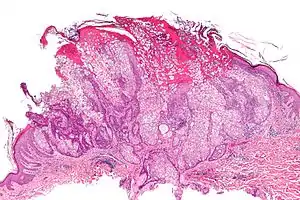

Sebaceous adenoma

A sebaceous adenoma, a type of adenoma, a cutaneous condition characterized by a slow-growing tumor usually presenting as a pink, flesh-coloured, or yellow papule or nodule.[1]: 662 [2]

| Micrograph of a sebaceous adenoma. H&E stain. | |